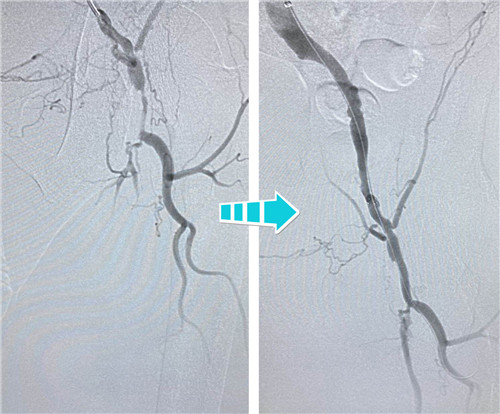

右側(cè)完全閉塞的髂血管順行開通無果,但這也難不倒我們經(jīng)驗豐富的鼓醫(yī)和石醫(yī)介入專家們,當即決定由“順穿”改行“逆穿”。逆穿導(dǎo)絲難度大,技術(shù)要求高,十分考驗術(shù)者的操作手法和預(yù)判,專家團隊經(jīng)過內(nèi)膜下破膜逆行,一次性準確對吻成功,同樣擴張球囊、植入支架,血流瞬間恢復(fù)暢通。